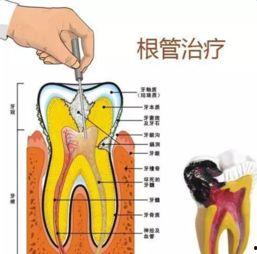

一、什么是根管治疗?

首先,得先弄清楚什么是根管治疗。简单来说,根管治疗就是治疗牙髓炎、根尖周炎等牙髓疾病的一种方法。当牙齿内部的神经和血管受到感染或损伤时,就需要进行根管治疗,将感染的牙髓清除,然后用药物填充根管,防止感染再次发生。

1. 治疗过程

我看了几个根管治疗视频,发现治疗过程其实并不复杂。首先,医生会用局部麻醉剂让你放松,然后使用特殊的工具清除牙髓。这个过程可能会有些不适,但麻醉剂会帮你减轻疼痛。

2. 治疗工具

视频里展示了各种治疗工具,比如根管锉、根管探针等。这些工具看起来有点吓人,但医生会小心翼翼地使用它们,确保治疗过程顺利进行。